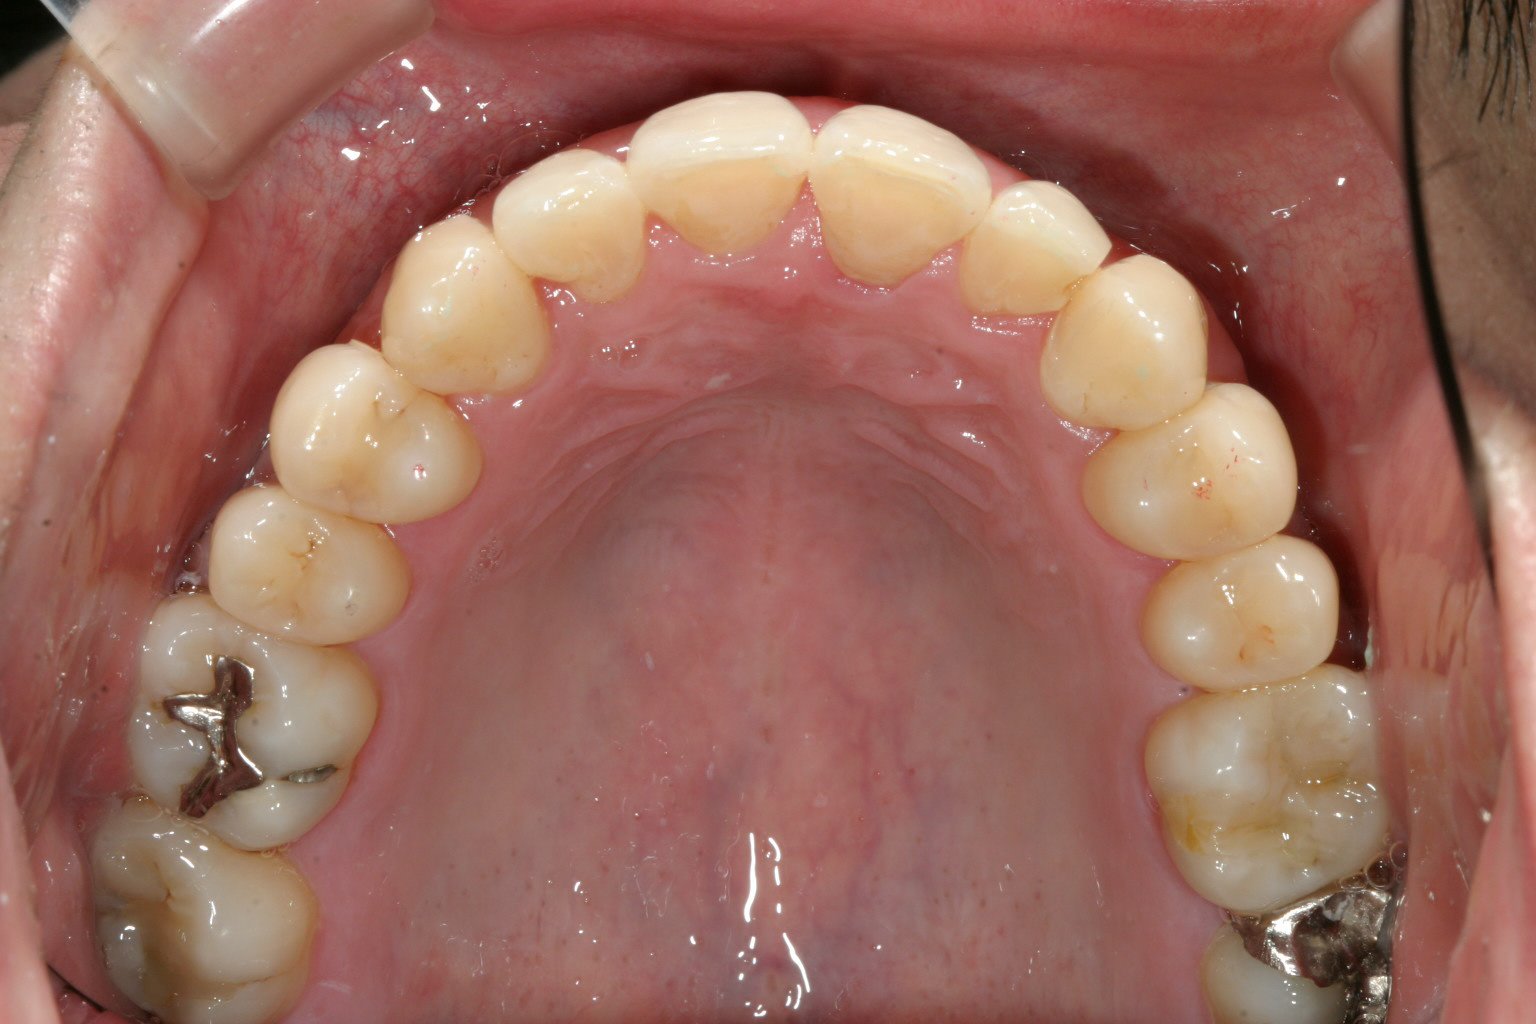

アーチがV字の為4本の前歯が並ばず叢生が激しいです。

綺麗にアーチが改善しました。